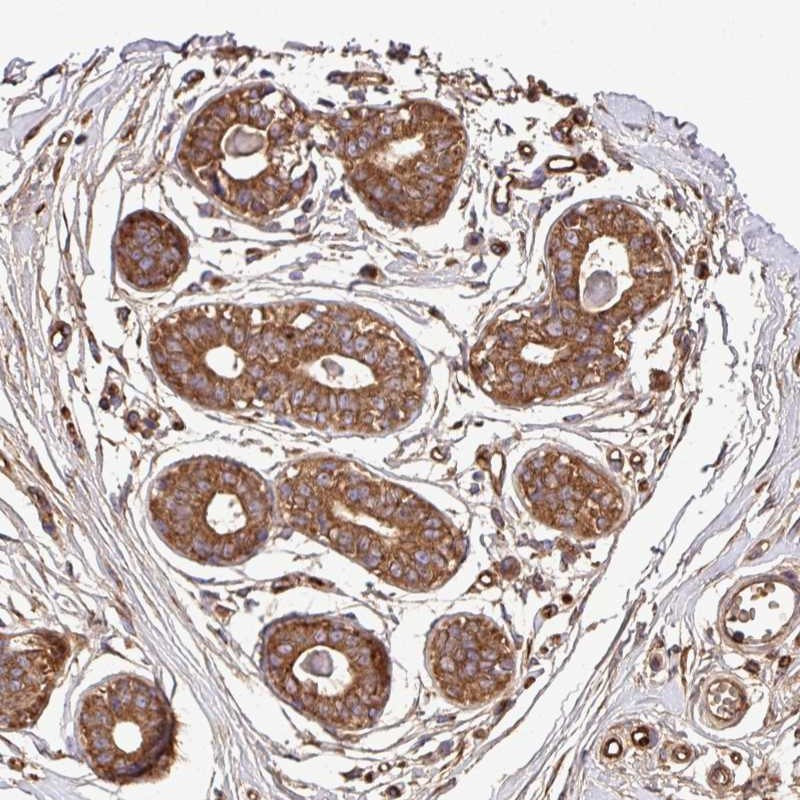

Immunohistochemical staining of human breast shows strong cytoplasmic positivity in glandular cells.